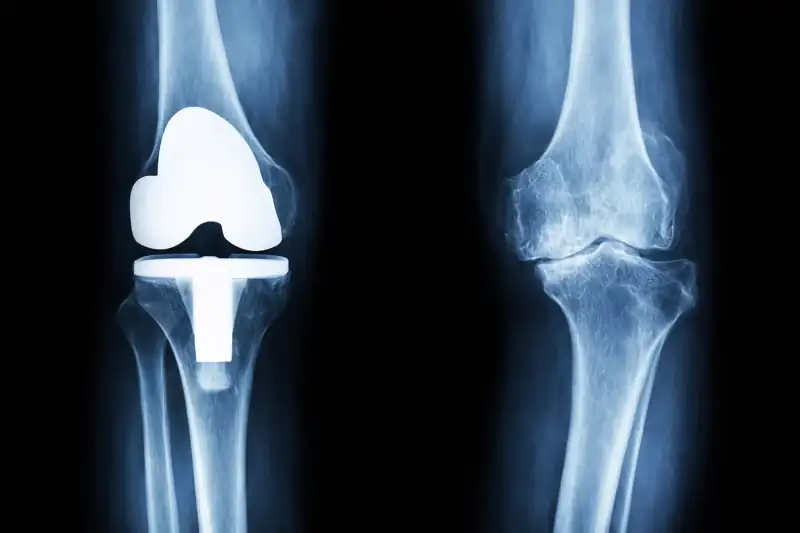

Prof. Pipino Gennaro, outsider a livello internazionale nella Chirurgia protesica di ginocchio mediante sistemi digitali ed intelligenza artificiale nel rispetto degli assi meccanici ed il ripristino totale della anatomia e cinematica del ginocchio protesizzato.

Il Prof. Pipino Gennaro mette a disposizione dei propri pazienti un’esperienza clinica di oltre 25.000 interventi, coniugando la maestria della chirurgia tradizionale con le tecnologie più avanzate del settore ortopedico.

protesi

al ginocchio